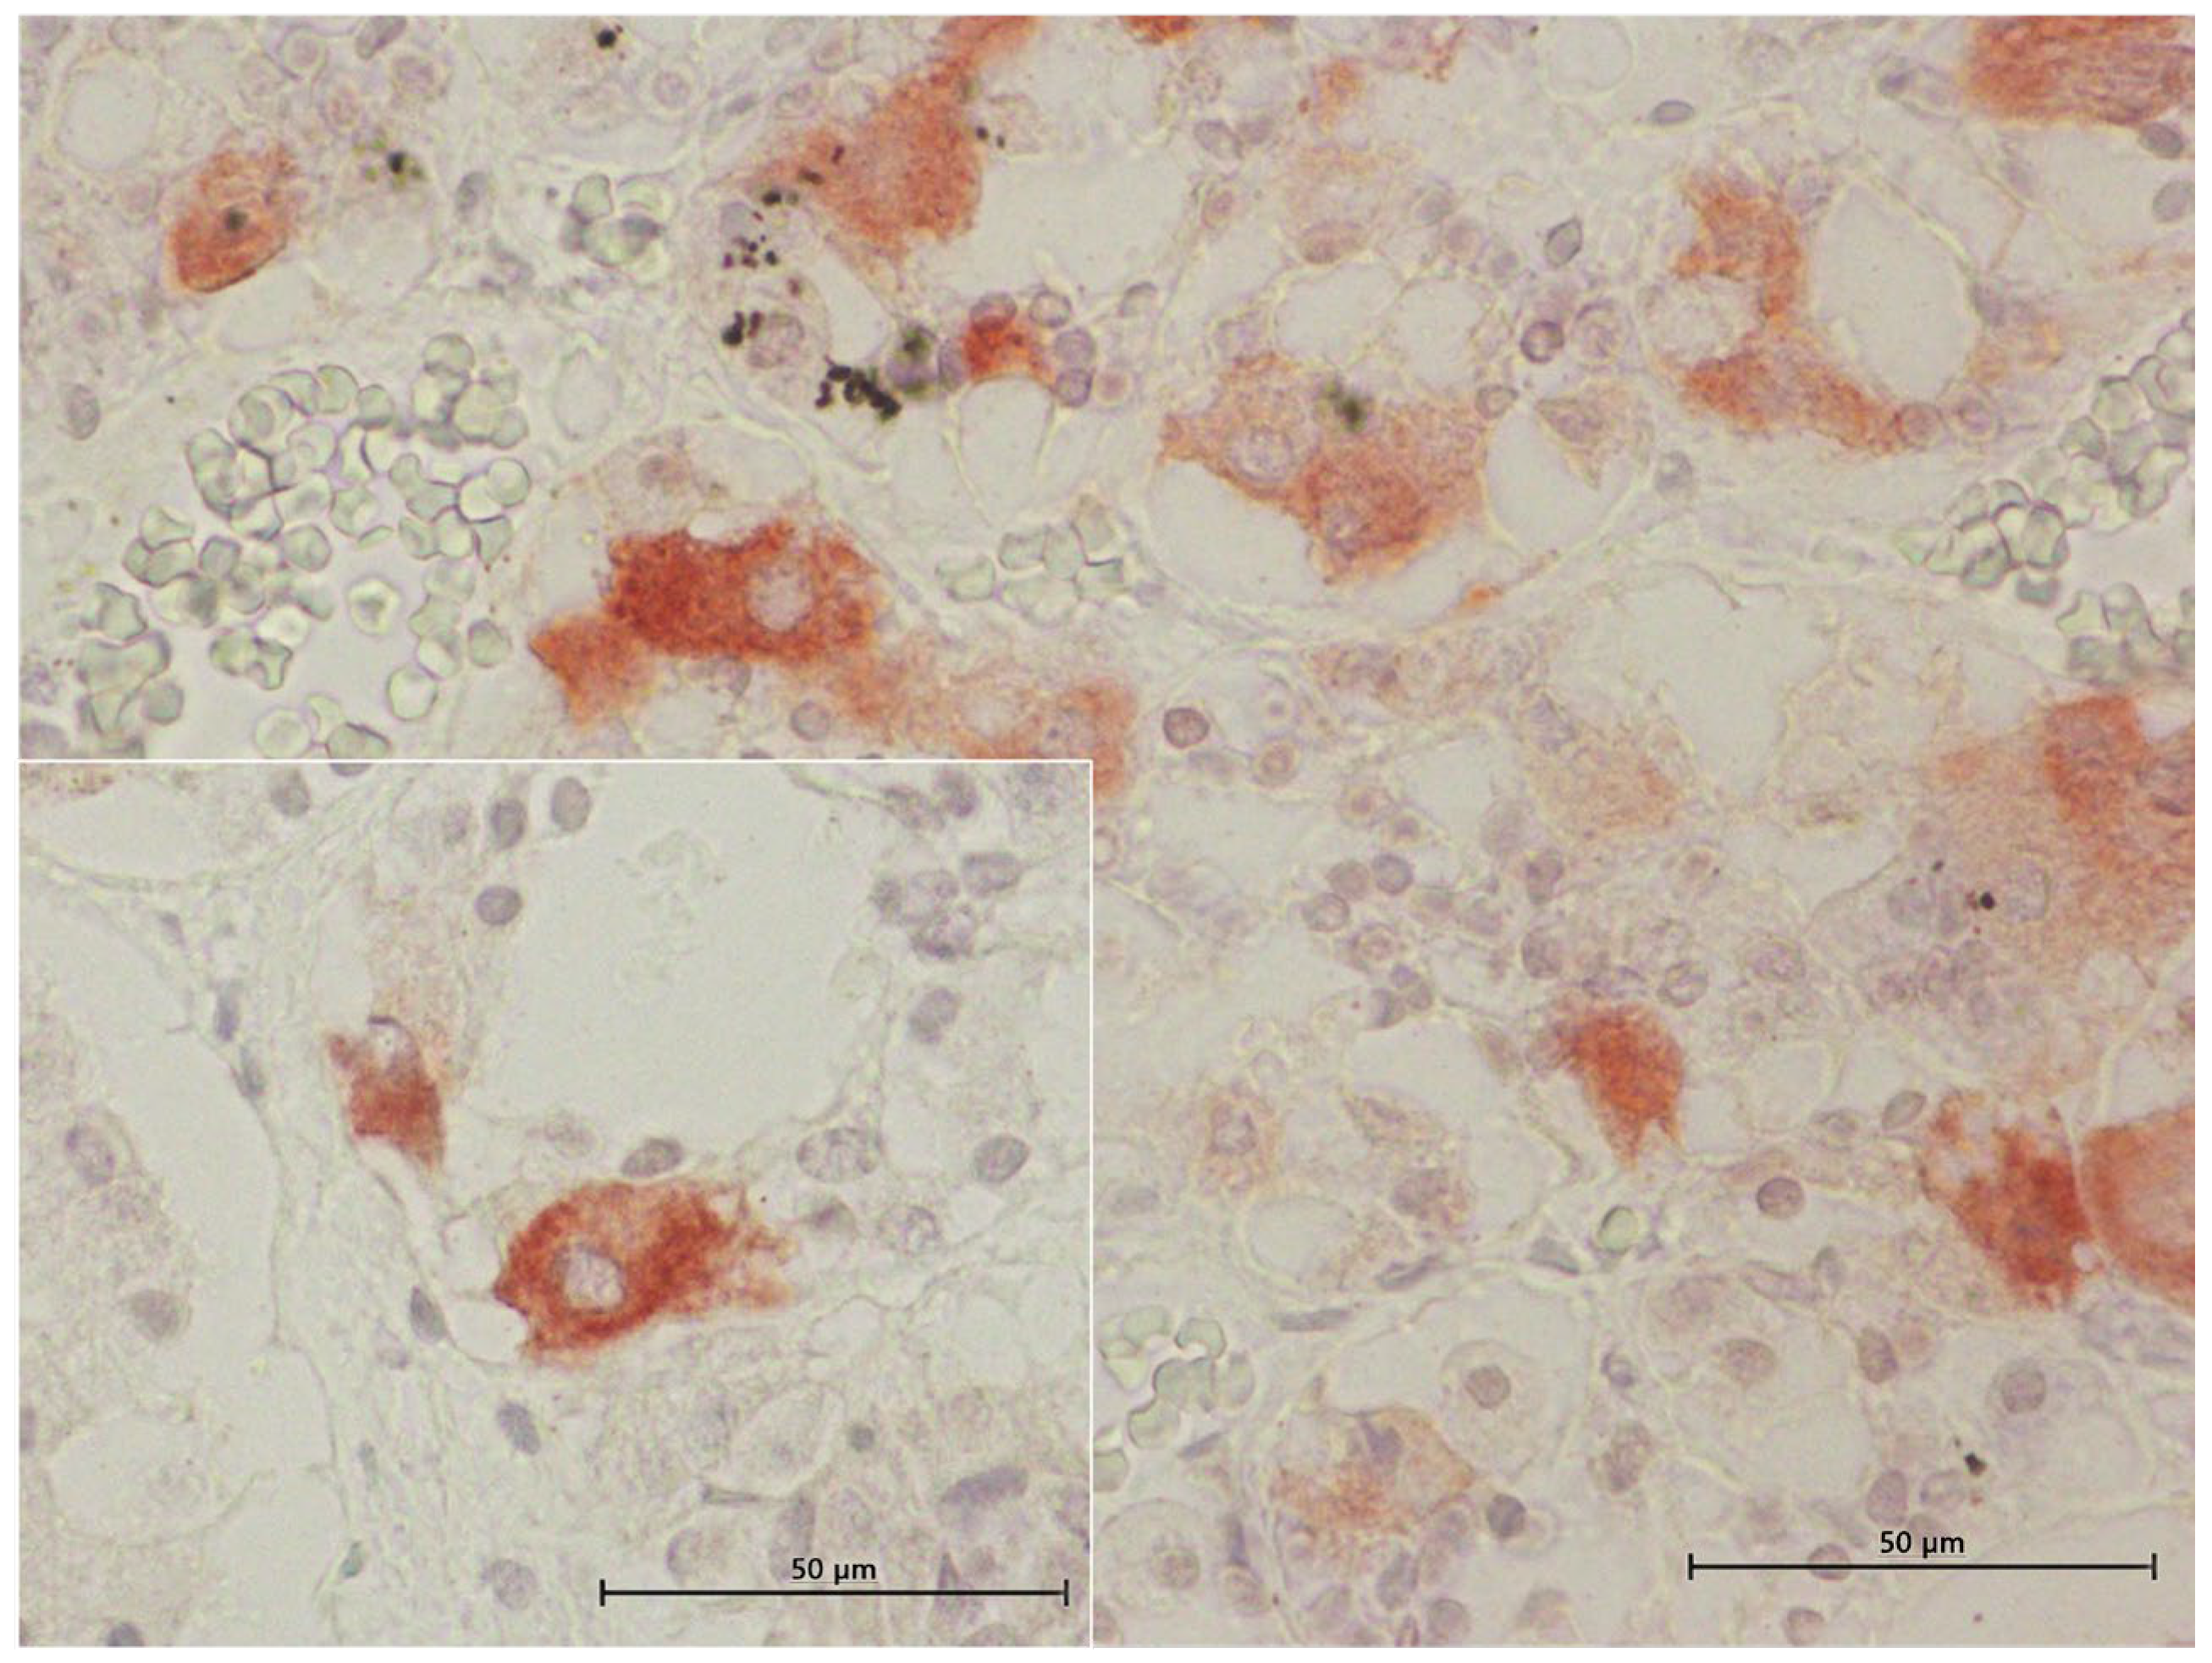

3.4. Inmunohistochemical Study

3.4.1. ACTH Labelling

3.4.2. MSH Labelling

3.4.3. TSH Labelling

4.2. Morphological and Inmunohistochemical Insights